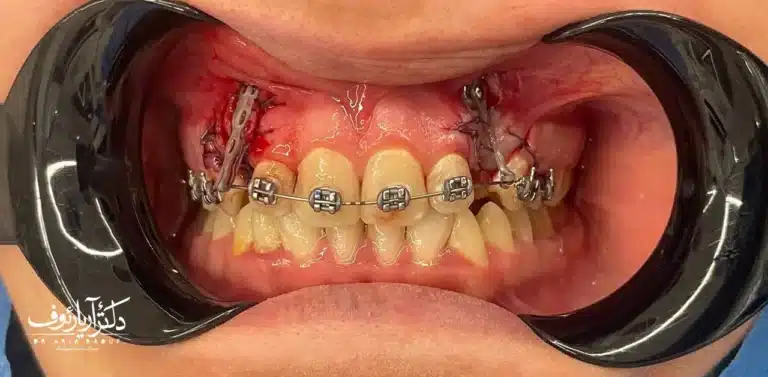

آلبوم تصاویر: حتماً از دکتر بخواهید عکسهای “قبل و بعد” کیسهای مشابه شما را نشان دهد. به جزئیات دقت کنید: آیا خط لبخند هماهنگ است؟ آیا دندانها کاملاً جفت شدهاند؟